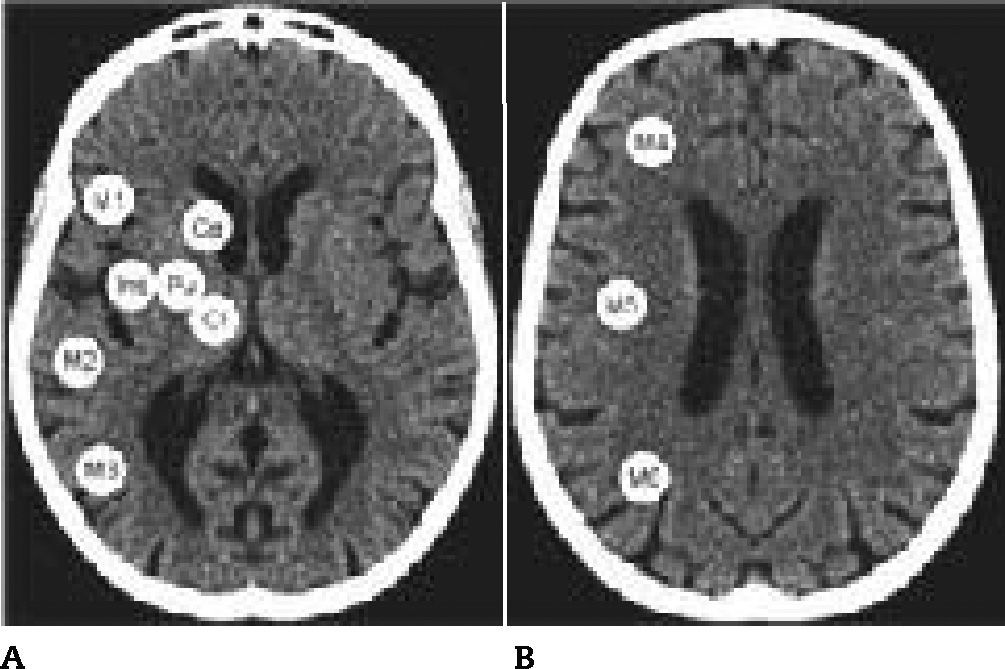

Utilizamos un tomógrafo helicoidal de 64 pistas Toshiba Alquilon 64 (cortes continuos de 5mm, 120 Kv, corriente de tubo de 225 mAs). Los valores de la ventana fueron optimizados para la distinción entre sustancia gris y sustancia blanca (80 UH). Evaluamos los dos cortes estándar del ASPECTS en las 10 TC: el primero al nivel del tálamo/ ganglios basales y el segundo adyacente al límite superior de las estructuras ganglionares. El primer corte incluye 7 regiones ASPECTS y el segundo contiene tres (fig. 1). Las 10 regiones se encuentran en el territorio de la arteria cerebral media. El ASPECTS se calcula partiendo de una puntuación inicial de 10 puntos, a la que se le va restando un punto por cada región con evidencia de hipoatenuación o edema. Dado que el edema representaría penumbra isquémica y no infarto cerebral, decidimos basar la puntuación solamente en la presencia o ausencia de hipodensidad4,5. La mejor puntuación ASPECTS es 10 (normal) y la peor es 0. La dicotomización en <7 o ≥7 define los grupos de mal y buen pronóstico, respectivamente1.

– Guía para la construcción de la matriz digital y para la evaluación visual. La figura muestra las 10 regiones de cada hemisferio. En el primer corte (A): M1, M2, M3, ínsula (Ins), putamen (Pu), cápsula interna (CI) y caudado (Ca). En el segundo corte (B): M4, M5 y M6. La guía fue construida mediante el montaje de un hemisferio copiado en espejo y simulando el contralateral para facilitar la observación mediante imágenes perfectamente simétricas.